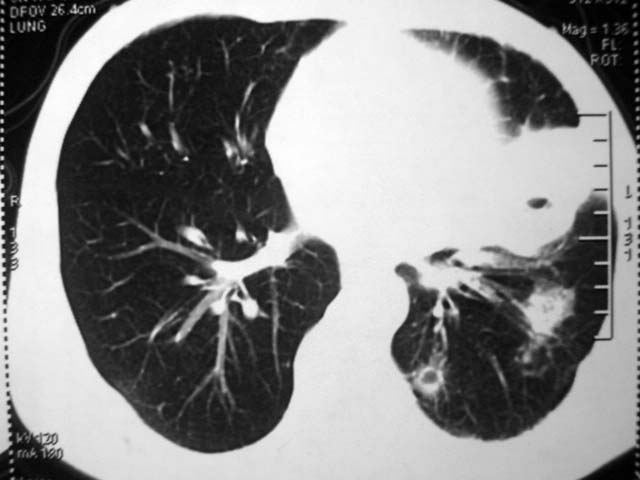

标题: CT17875:肺曲霉菌病?结核? [打印本页]

标题: CT17875:肺曲霉菌病?结核?

男,52岁,发热2月,糖尿病史。

抗结核治疗irpz方案,血糖未治疗,空腹15.9左右。症状无好转,左胸痛。

复查ct

2、双肺见多发片状及结节状高密度影,大多数病灶中心均见“空泡征”。

结果:两肺继发性肺结核并曲霉菌感染。